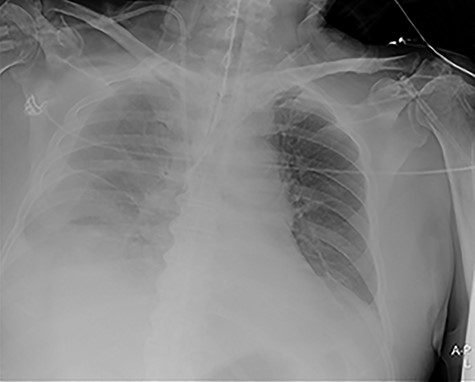

A 74-year-old male patient with a history of type 2 diabetes mellitus, ankylosing spondylitis and cystoprostatectomy with Bricker bladder was admitted with acute renal failure not responding to conservative measures. He needed haemodialysis. Due to clinical deterioration with dyspnoea, hypotension and inadequate peripheral perfusion during intermittent haemodialysis, he was transferred to the intensive care unit (ICU). A right-sided pleural effusion was found, and the intensivist inserted a pigtail pleural drain under ultrasound guidance. The fluid was somewhat bloody, but control with ultrasound and CXR (Fig. 1) after the procedure was normal.

Portable chest X-ray with no pleural effusion after placement of pigtail pleural drain.